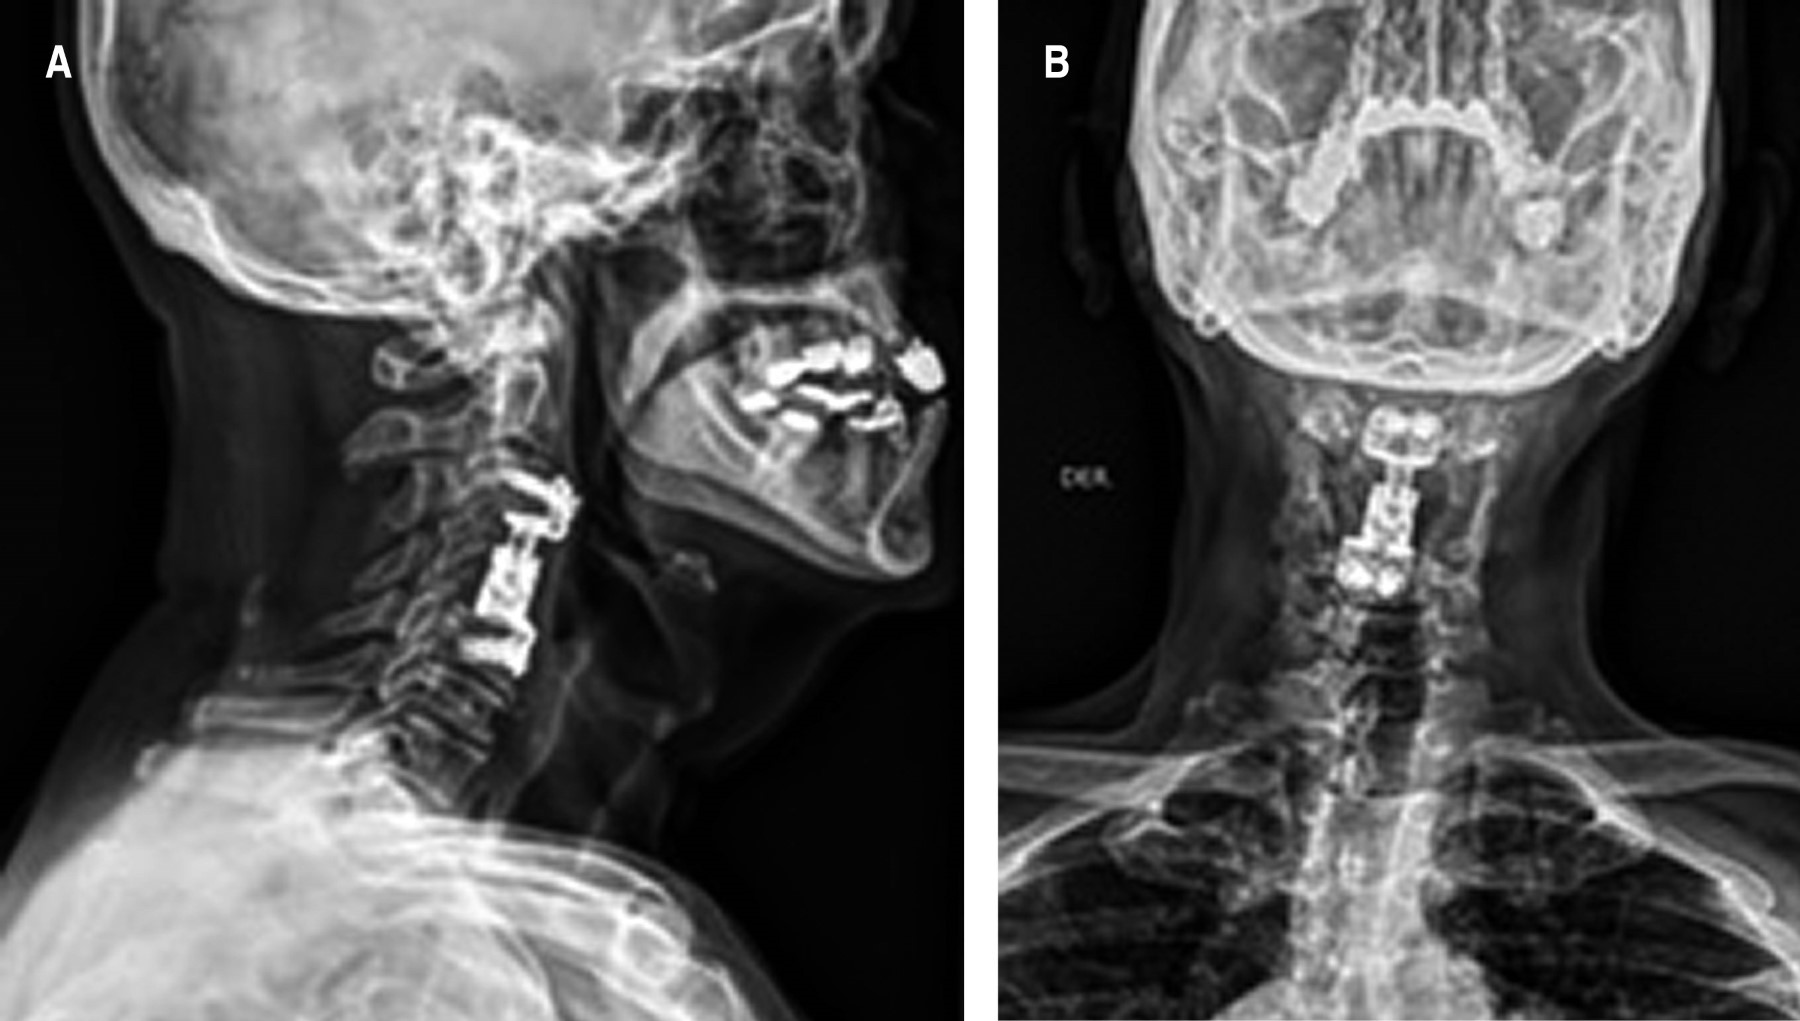

Fue llevado a sala de operaciones, donde se realizó corpectomía vertebral de C4, con colocación de prótesis de cuerpo vertebral de C3 a C5 (Figura 2A-B), teniendo sangrado transoperatorio (3,700 ml), siendo necesaria la transfusión de hemoderivados. Al evaluar cuerpo vertebral C4 se observa tejido blando sumamente vascularizado.

Al momento de incidir columna vertebral y evaluar la destrucción total del cuerpo vertebral, el diagnóstico oncológico fue un reto. Las metástasis a columna vertebral provocan dolor radicular y déficit neurológico progresivo, parálisis completa, y déficit esfinteriano.13 Cuando se afecta el hueso vertebral, las consecuencias son repercusiones mecánicas y estructurales importantes, incluyendo fracturas por compresión, deformidades, subluxaciones y listesis.13-15 Se colocó una prótesis de cuerpo vertebral para garantizar la estabilidad de la columna tras la corpectomía total.16

En el procedimiento realizado se colocó al paciente una prótesis metálica para proporcionarle movilidad y estabilidad cervical, evitando de esta manera la aparición de subluxaciones. Al ser una lesión muy vascularizada, sería ideal embolizarla para evitar hemorragia transoperatoria.